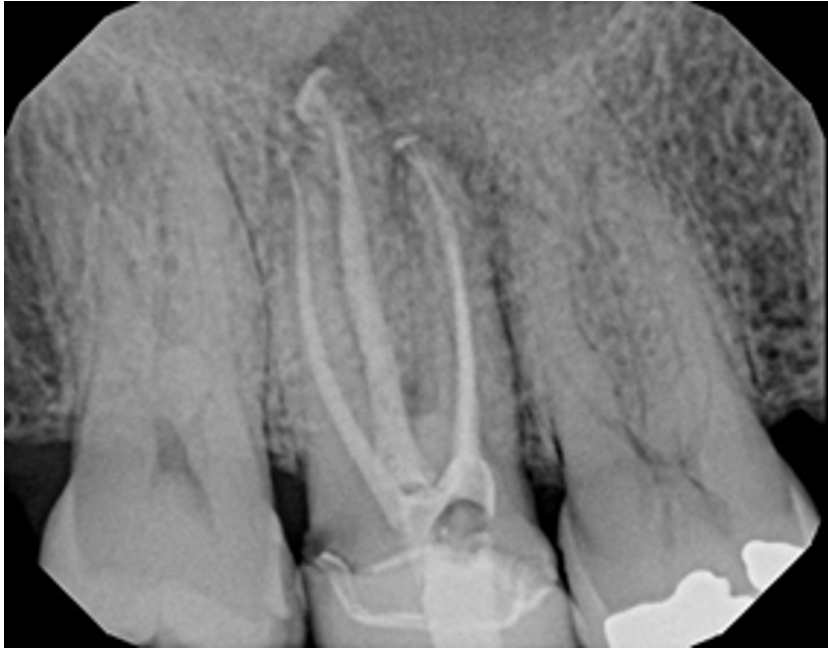

Examples of X-Ray scoring

(Group A – Odne Clean)

Score 4 – Simple anatomy with apical delta // Score 6 – Curved anatomy + lateral canal in middle third

Score 7 – Curved anatomy + lateral canal in apical third // Score 8 – Curved anatomy with apical delta